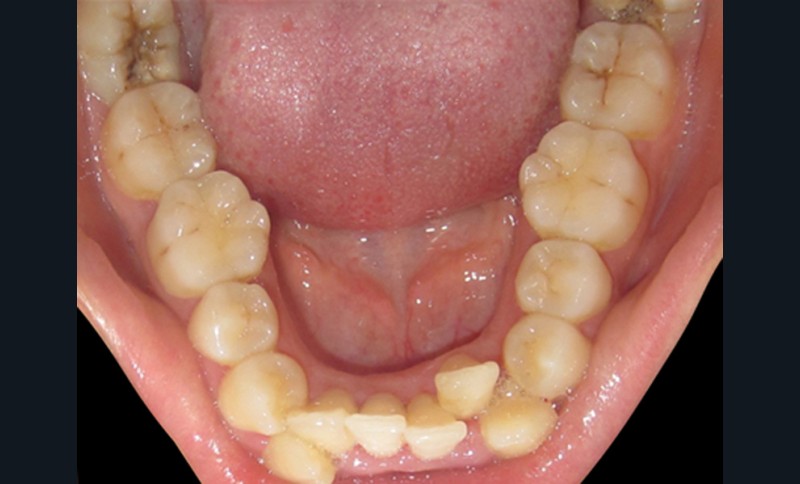

Manque d’espace en distal de la 2e molaire

Il est très important d’évaluer la distance rétromolaire avant l’indication de l’extraction de dents de sagesse incluses pour éviter des extractions abusives et systématiques (manque de bénéfices démontrés et procédures qui ne sont pas sans risques) (fig. 2).